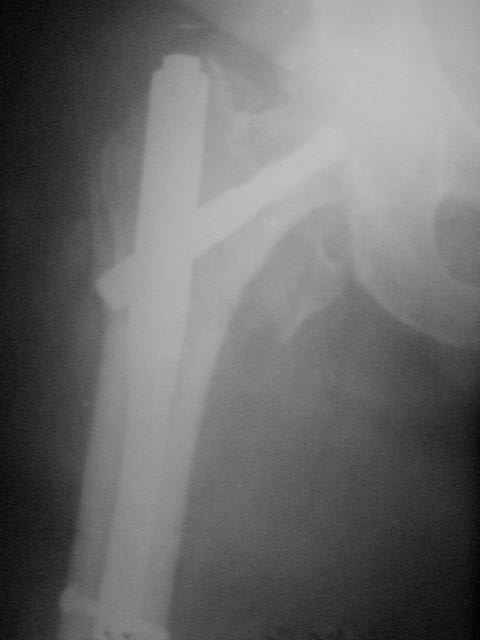

Не думаю так. см вложение.

> Не думаю так. см вложение.

Для такого перелома вполне может быть использован диафизарный штифт, который отечественного производства я даже боюсь считать во сколько раз дешевле... Недавно несколько примеров я закидывал.